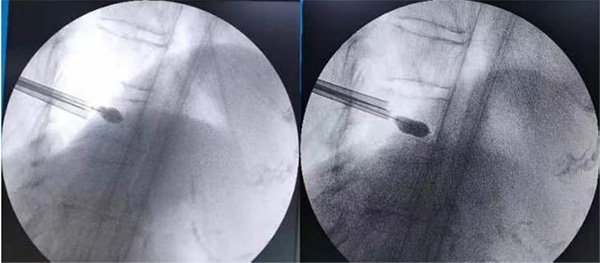

图为术中球囊撑开、骨折复位